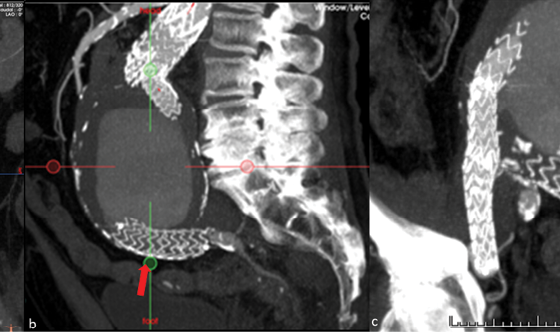

This case refers to an 88-year-old Caucasian male who underwent EVAR in 2010, eleven years prior to the current presentation. His past medical history included hypertension, dyslipidemia, hyperuricemia, and hypothyroidism. He did not comply with his annual post-EVAR follow up for an unknown number of years. A routine abdominal ultrasound revealed an 11 cm aneurysm, and the patient was referred to our department. At presentation, the patient was asymptomatic and his routine laboratory values were within normal ranges. An urgent contrast-enhanced computed tomographic angiography (CTA) scan confirmed the 11cm abdominal aortic aneurysm. The CTA also demonstrated disconnection of the left limb from the main graft body, with loss of distal fixation and aneurysms of both the left CIA artery and the left IIA (3.2cm and 2.4cm respectively). Also, the right limb of the previous endograft was extended to the right EIA (Fig 1).

The procedure was performed under general anesthesia with bilateral surgical cut-down for arterial access. Initially, a 36mm TREO aorto-uni-iliac (AUI) endograft (Terumo, Somerset, NJ) was deployed through the right limb of the previous graft (Fig 2). The second step was the construction of a femoro-femoral bypass from right to left using an 8mm PTFE ringed graft. The last planned step would be the placement of a reverse U-stent graft via ipsilateral left CFA access. The initial attempts to advance the stent graft within the IIA failed due to the steep angulation of the IIA origin and the insufficient support due to the largely aneurysmal CIA. A molding balloon, which temporarily sealed the left CIA, facilitated insertion of a 0.035’ stiff hydrophilic guidewire (Terumo, Japan) deep within the left aneurysmal IIA before the deployment of the reverse U-stent (Viabahn 8X100 mm and 10×50 mm) (Fig 3). Completion angiography demonstrated the complete exclusion of all three aneurysms without any signs of endoleak. Aneurysms’ exclusion without endoleak was also confirmed at 1-month follow up CT angiography.

In the herein presented case the challenge was to treat simultaneously both the type IIIa endoleak and the IIA aneurysm, as the IIA was the only vessel providing perfusion to the pelvis. Due to the acute angulation of the IIA origin, the advancement of the stent graft within the IIA was not possible even with the use of a super stiff 0.035’ guide wire. Therefore, after placing a stiff hydrophilic guide wire deep within the IIA, a CIA occlusion technique with a molding balloon was used to occlude the aneurysmal CIA and provide support for the advancement of stent graft across the IIA origin, and distal to the aneurysm, as to achieve efficient exclusion.